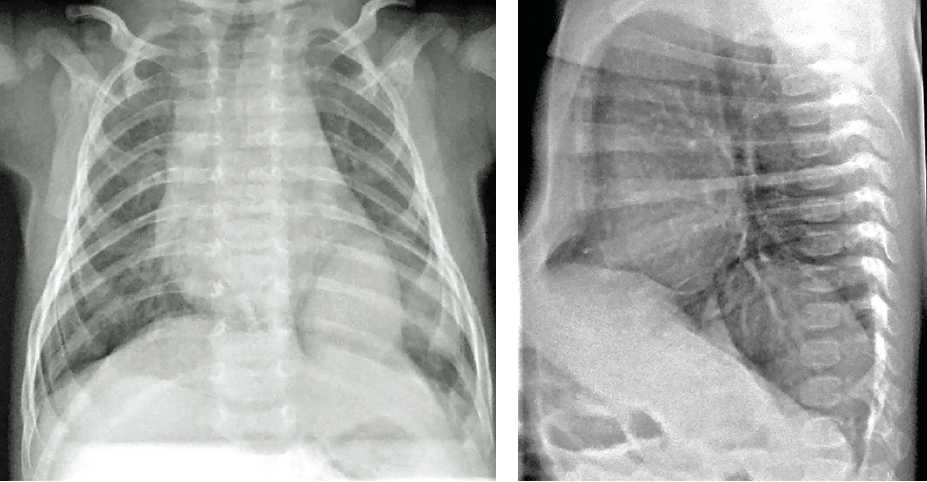

Michael W. Cater, MD

Chest radiographs were obtained from a 2-month-old boy who was admitted to the hospital for evaluation and management of inspiratory stridor, which had begun at 4 to 6 weeks of age.